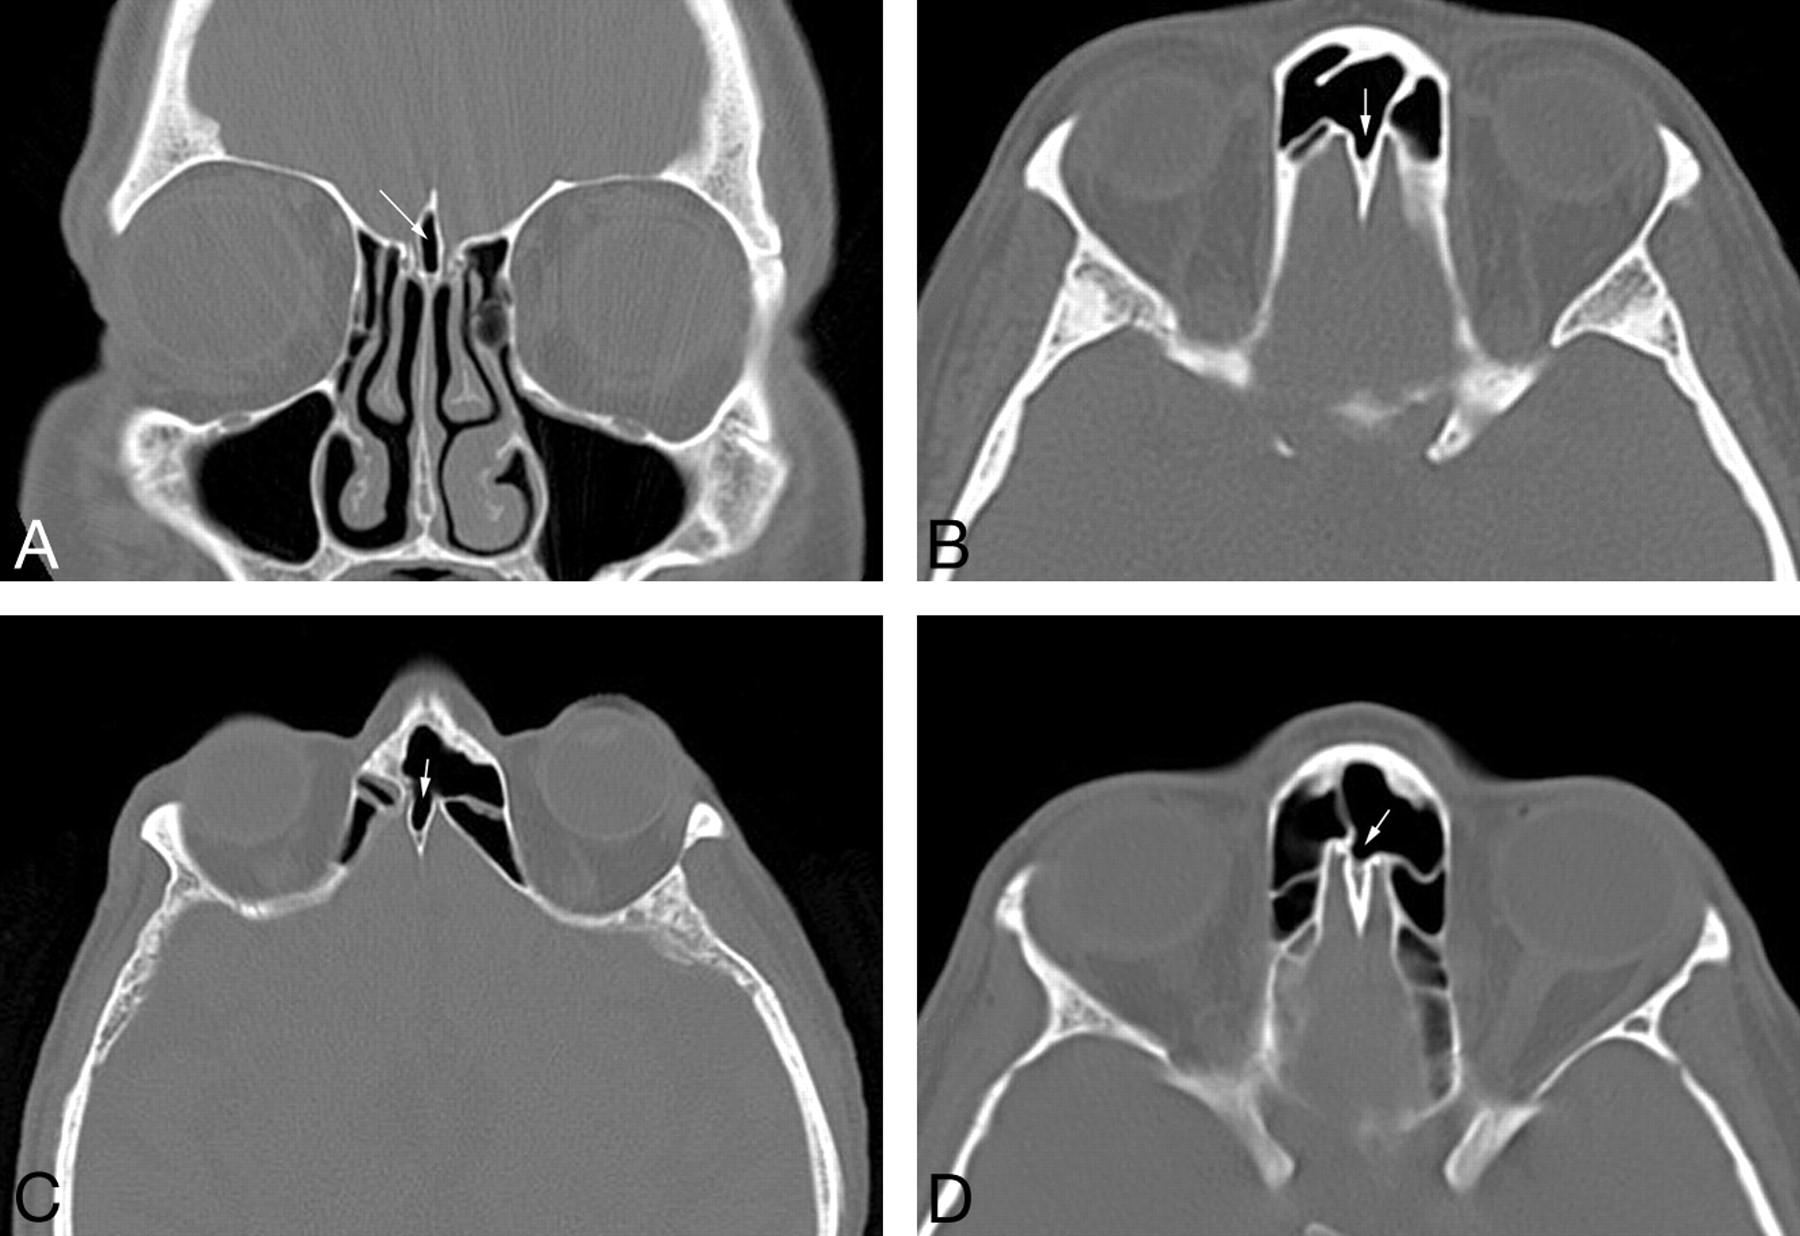

Of the 200 CT scans in adults, there were 26 with some degree of pneumatization of the crista galli (13%). There were 4 cases with only minimal pneumatization and 22 cases with extensive pneumatization (Fig 1). In all cases, the pneumatizing air cell was either the left (11 cases) or right (15 cases) frontal sinus and the crista galli was pneumatized from its anteriormost surface. In 2 cases, inflammatory disease in a frontal sinus extended directly into the pneumatized crista galli (Fig 2).

A, Coronal CT scan of the paranasal sinuses in a 45-year-old women with difficulty breathing shows the typical appearance of crista galli pneumatization (arrow). B, Axial CT scan of the paranasal sinuses in a 51-year-old man with sinus pain shows extensive pneumatization of the crista galli from the right frontal sinus (arrow). C, Axial CT scan of the paranasal sinuses in a 63-year-old man with difficulty breathing shows extensive pneumatization of the crista galli from the left frontal sinus (arrow). D, Axial CT scan of the paranasal sinuses in a 33-year-old woman with difficulty breathing shows minimal pneumatization of the anterior crista galli from the left frontal sinus (arrow).